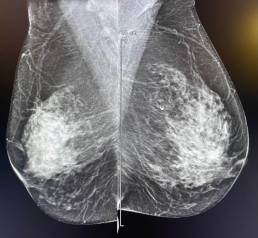

Patiente de 65 ans, mammographie de dépistage.

MammoScreen™ pointe une distorsion architecturale du sein droit.